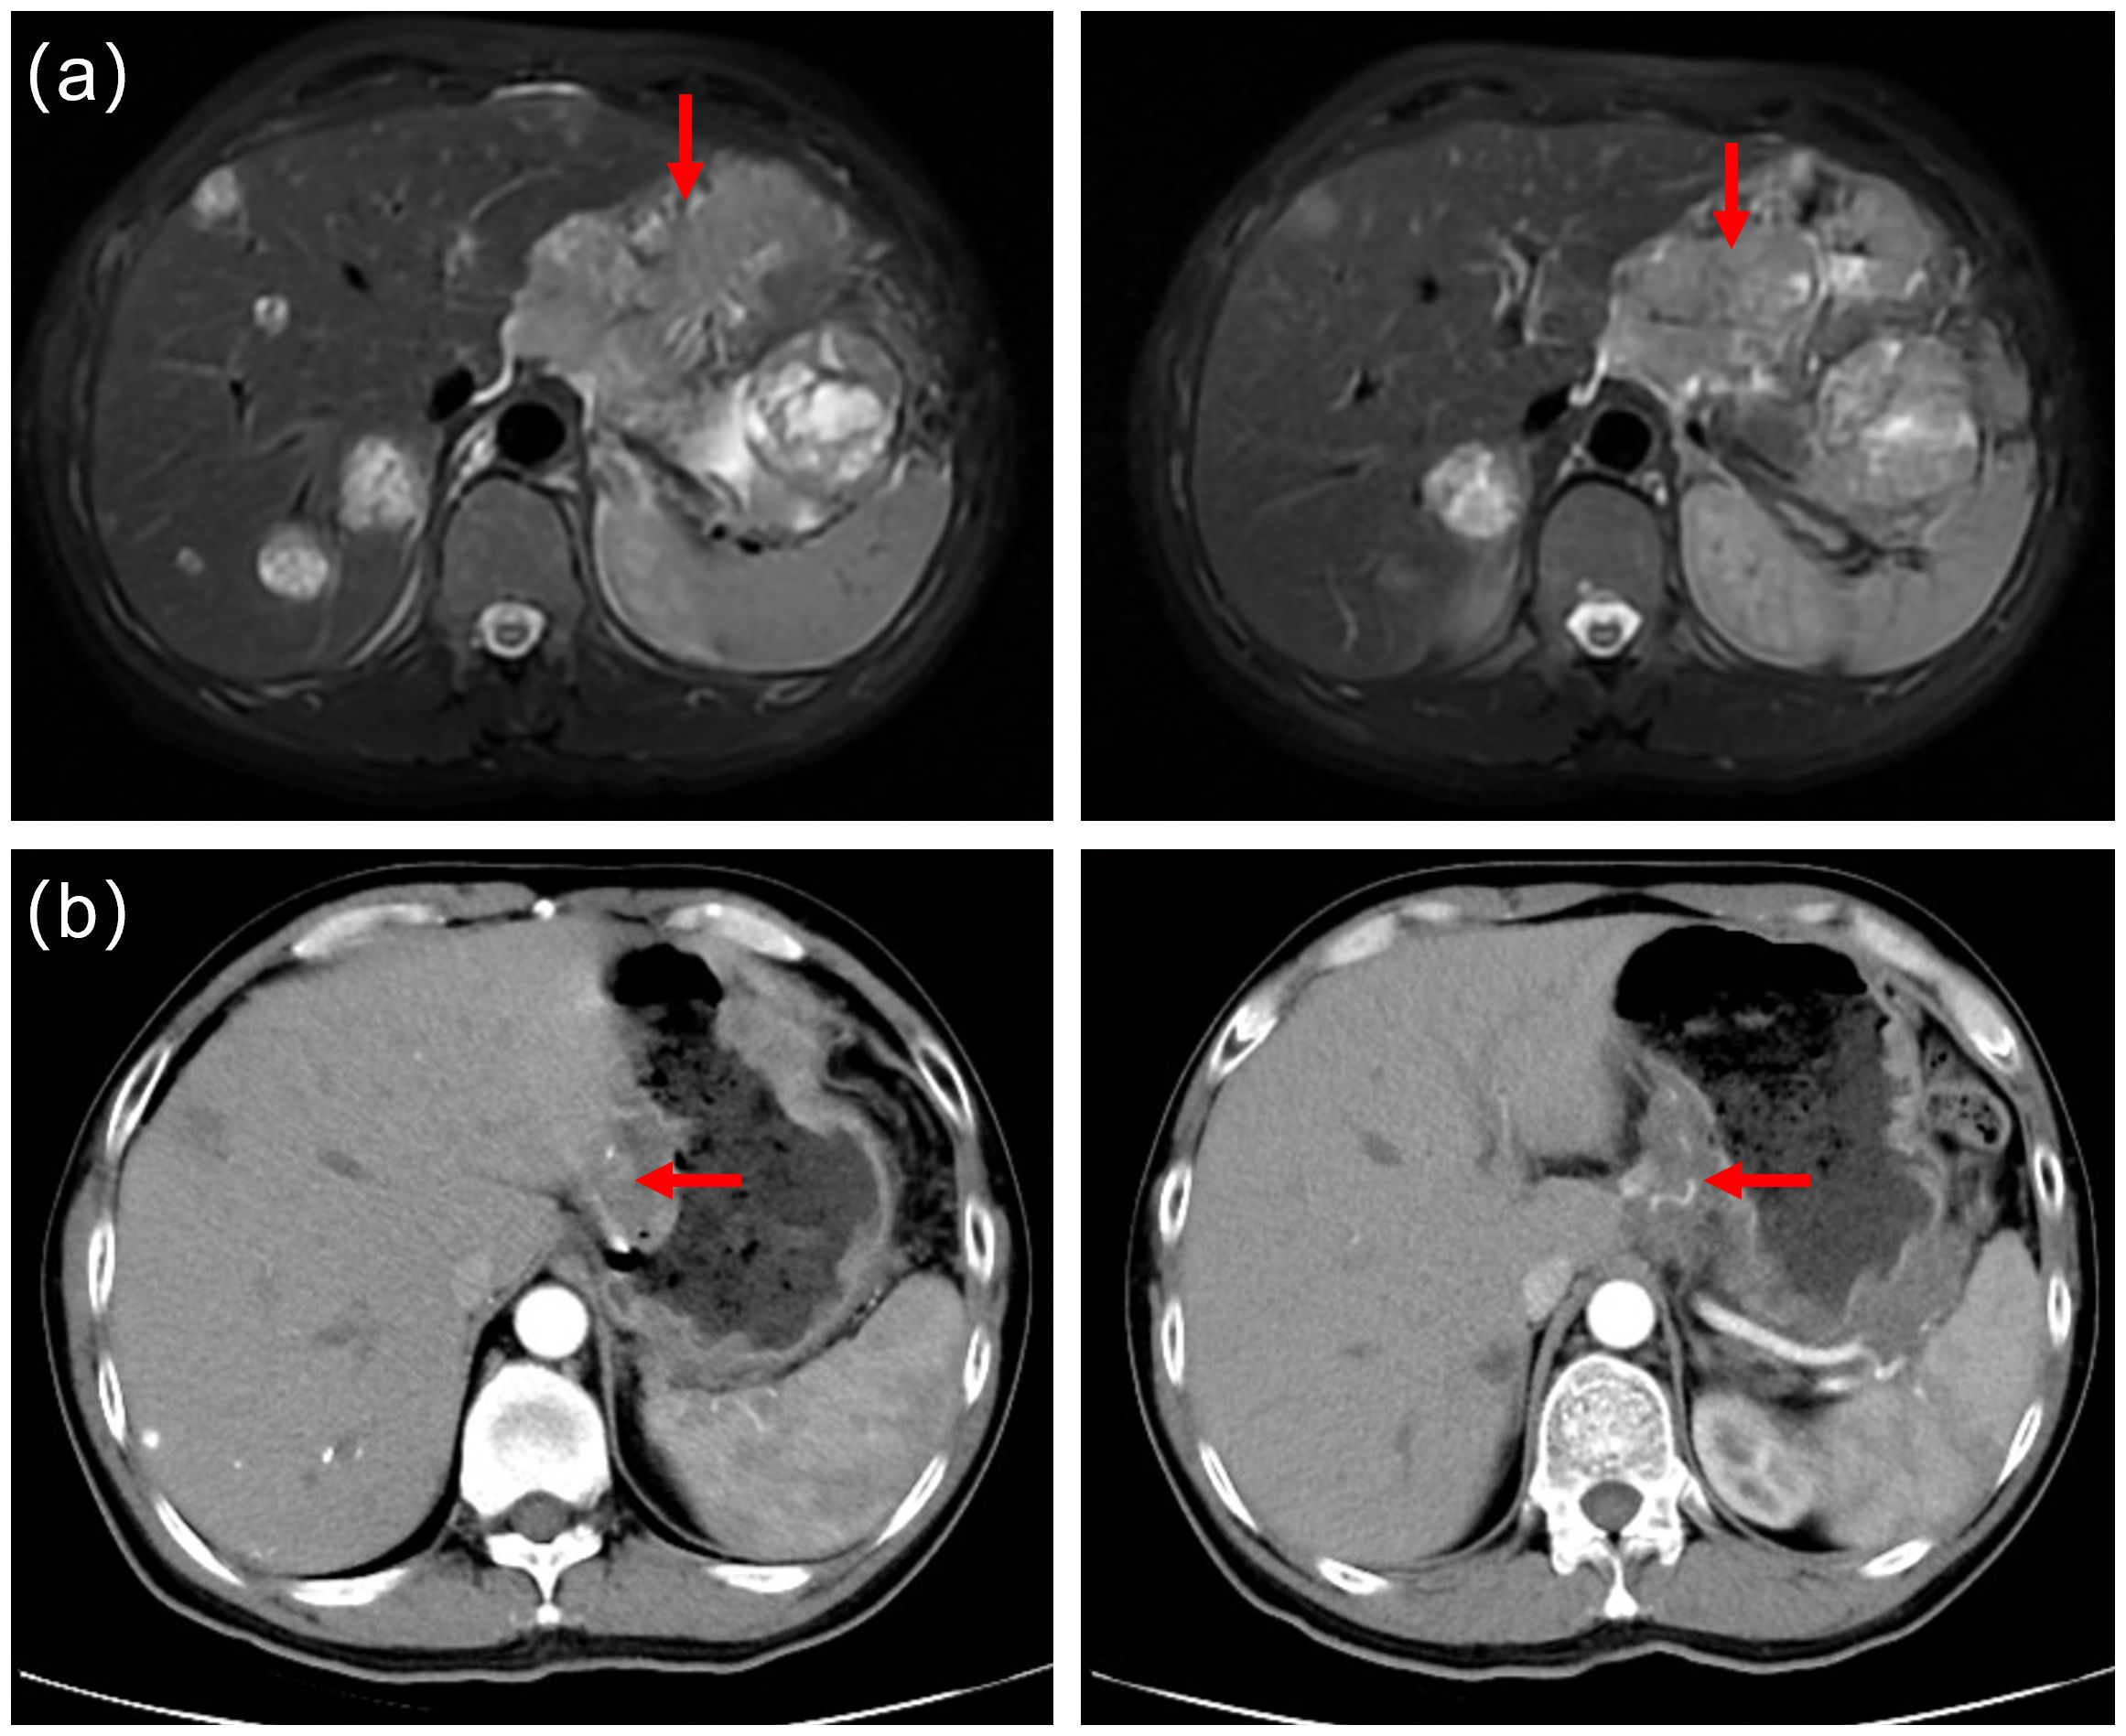

Routine follow-up examinations were conducted after two cycles of treatment, revealing a marked improvement in the patient’s condition. The serum AFP level markedly decreased, plummeting from >3630ng/ml to 103ng/ml (Figure 1). In August 2023, abdominal CT imaging further confirmed a substantial reduction in the liver lesion size, with the shortest diameter of the largest hepatogastric space lymph nodes shrinking from 46mm to 24mm(reduction by 47.83%) (Figure 2). The clinical outcome was classified as partial remission per the RECIST 1.1 guidelines.

Four-panel medical imaging comparison of a liver. Panel (a) shows two MRI scans highlighting a lesion with red arrows. Panel (b) displays two CT scans alsoindicating a similar area with red arrows. The shortest diameter of the largest hepatogastric space lymph nodes with red arrow shrunk from 46mm to 24mm (reduction by 47.83%).

Figure 2. (a) Prior to cryoablation, abdominal magnetic resonance imaging(MRI) identified multiple liver metastases and metastatic lymph nodes. (b) Follow-up computed tomography scans in August 2023 revealed a significantly reduced in liver tumor lesions. The shortest diameter of the largest hepatogastric space lymph nodes shrunk from 46mm to 24mm(reduction by 47.83%).